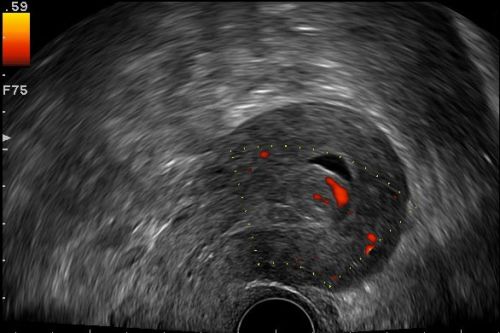

Physikalische & technische Grundlagen, Indikationen & Untersuchungstechnik, Sonoanatomie der Genitalorgane incl. Zyklus, Uterus myomatosus, Uterusanomalien, Adnextumoren, Endometriumpathologien, Frühgravidität (normale & gestörte Entwicklung), ektope Gravidität, Kasuistiken, ausreichend Zeit für Diskussionen, Fallbeispiele aus der Praxis